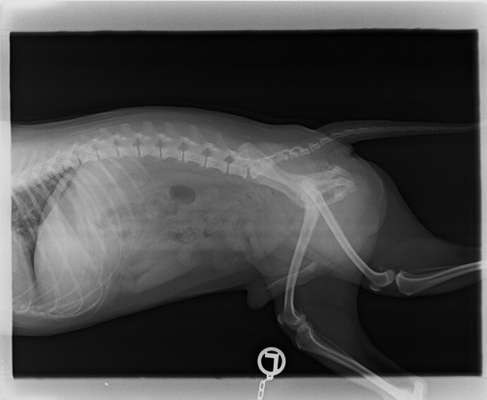

Zweite Frage: wurde noch eine andere Ebene geröntgt, d. h. gibt es ein oder mehrere weitere(s) Bild(er)?

Das ist das zweite

Das Röntgenbild ist leider ziemlich schlecht aufgenommen. Die Hüfte ist darauf komplett schief und verzogen.

Man kann zwar eine Art Zubildung am rechten Kopf erkennen, was das aber ist, kann man wegen der schlechten Aufnahme unmöglich sagen.

Zwei Anhaltspunkte würde ich orthopädisch verorten möglicherweise, allerdings ist schwer zu beurteilen, ob es durch die nicht optimale Lagerung für die Bilder verursacht ist. Das CT und höher auflösende Aufnahmen können da hoffentlich mehr Klarheit bringen. Wenn sich der Verdacht eures Arztes nicht bewahrheitet (was ich hoffe, aber davon hab ich auch keine Ahnung tatsächlich), würde ich alle Bilder, insbesondere die besseren, einem Orthopäden zur Beurteilung zur Verfügung stellen.